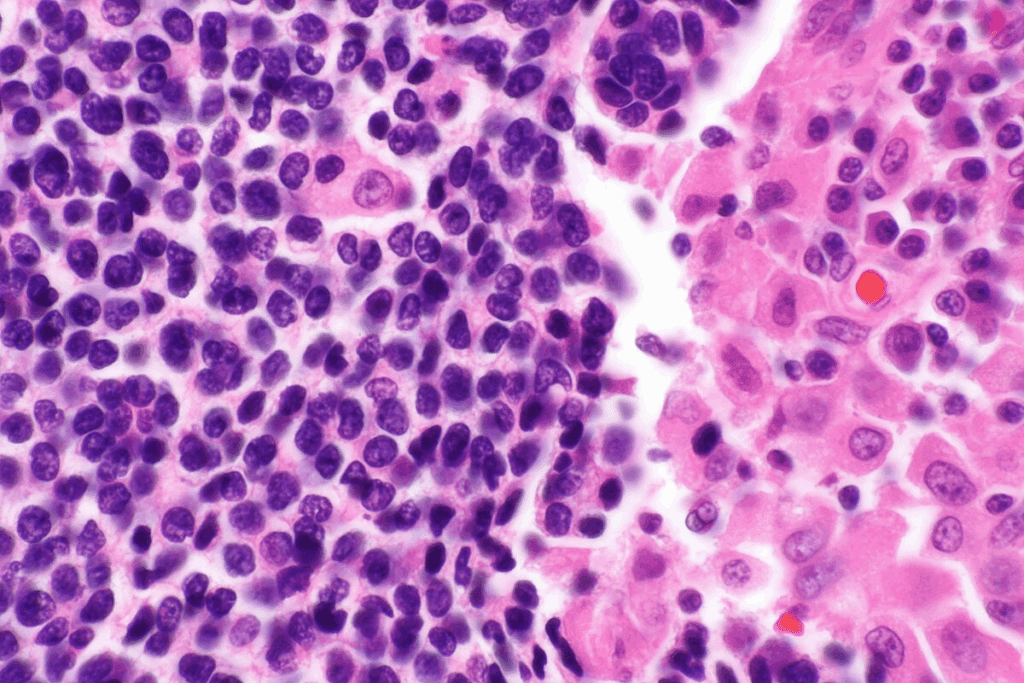

Urine Culture and Colony Count

Urine culture is the top way to find bacteria. It takes a urine sample and lets bacteria grow. Then, it counts how many grow, looking for ≥10^5 CFU/mL.

Table: Interpretation of Urine Culture Results

CFU/mL | Interpretation |

Contamination or insignificant bacteriuria | |

10^3 – 10^5 | Suspicious for bacteriuria; may require repeat testing |

≥10^5 | Significant bacteriuria |

Urinalysis Interpretation

Urinalysis is also important. It checks urine’s physical and chemical makeup. It looks for signs of infection like pH and nitrite. But, it’s not always right, as some tests can be wrong.

Advanced Diagnostic Methods

For tricky cases, we use advanced tests. PCR and MALDI-TOF can quickly find and identify bacteria. This helps doctors treat the right bug fast.

Using all these tests together helps doctors find and treat bacteria early. This keeps patients safe and healthy.